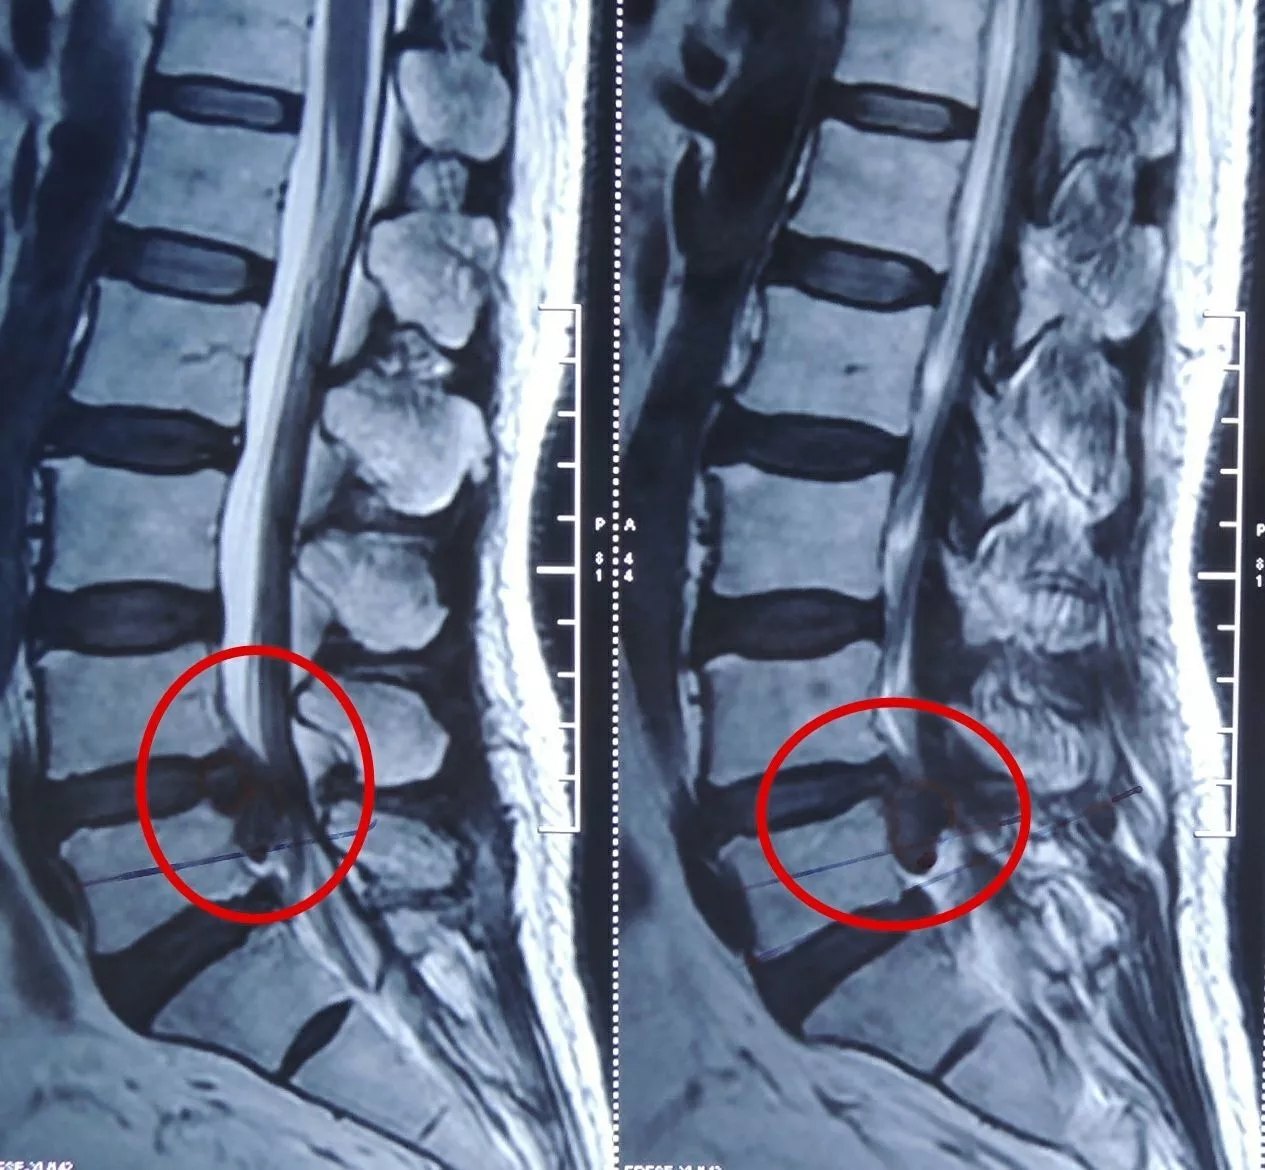

张xxx 男 39岁.腰二三椎间盘突出 严重挤压马尾神经病例

腰椎间盘突出症,术后复查突出髓核消失.这个患者,女性,42岁 - 抖音

男.52岁 典型腰椎间盘突出症病例